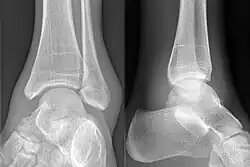

Diagnostische Kriterien im Röntgenbild sind:

- fehlende tafelartige leicht konkave Trochlea tali (Sprungbeinrolle)

- konvexe, bogig-gerundete Trochlea

- der Trochleaform angepasste atypische Konfiguration der Sprunggelenksgabel.[1]